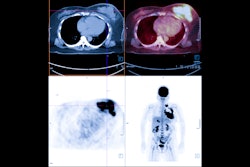

The update also features Hermes’ Theranostic Dashboard for optimizing patient-specific activity injections while ensuring safe dose limits for all available radiopharmaceuticals, the Selective Internal Radiation Therapy (SIRT) application for dosimetry planning and verification, and the Lung Lobe Quantification (LLQ) tool, which includes a new lung segmentation algorithm.